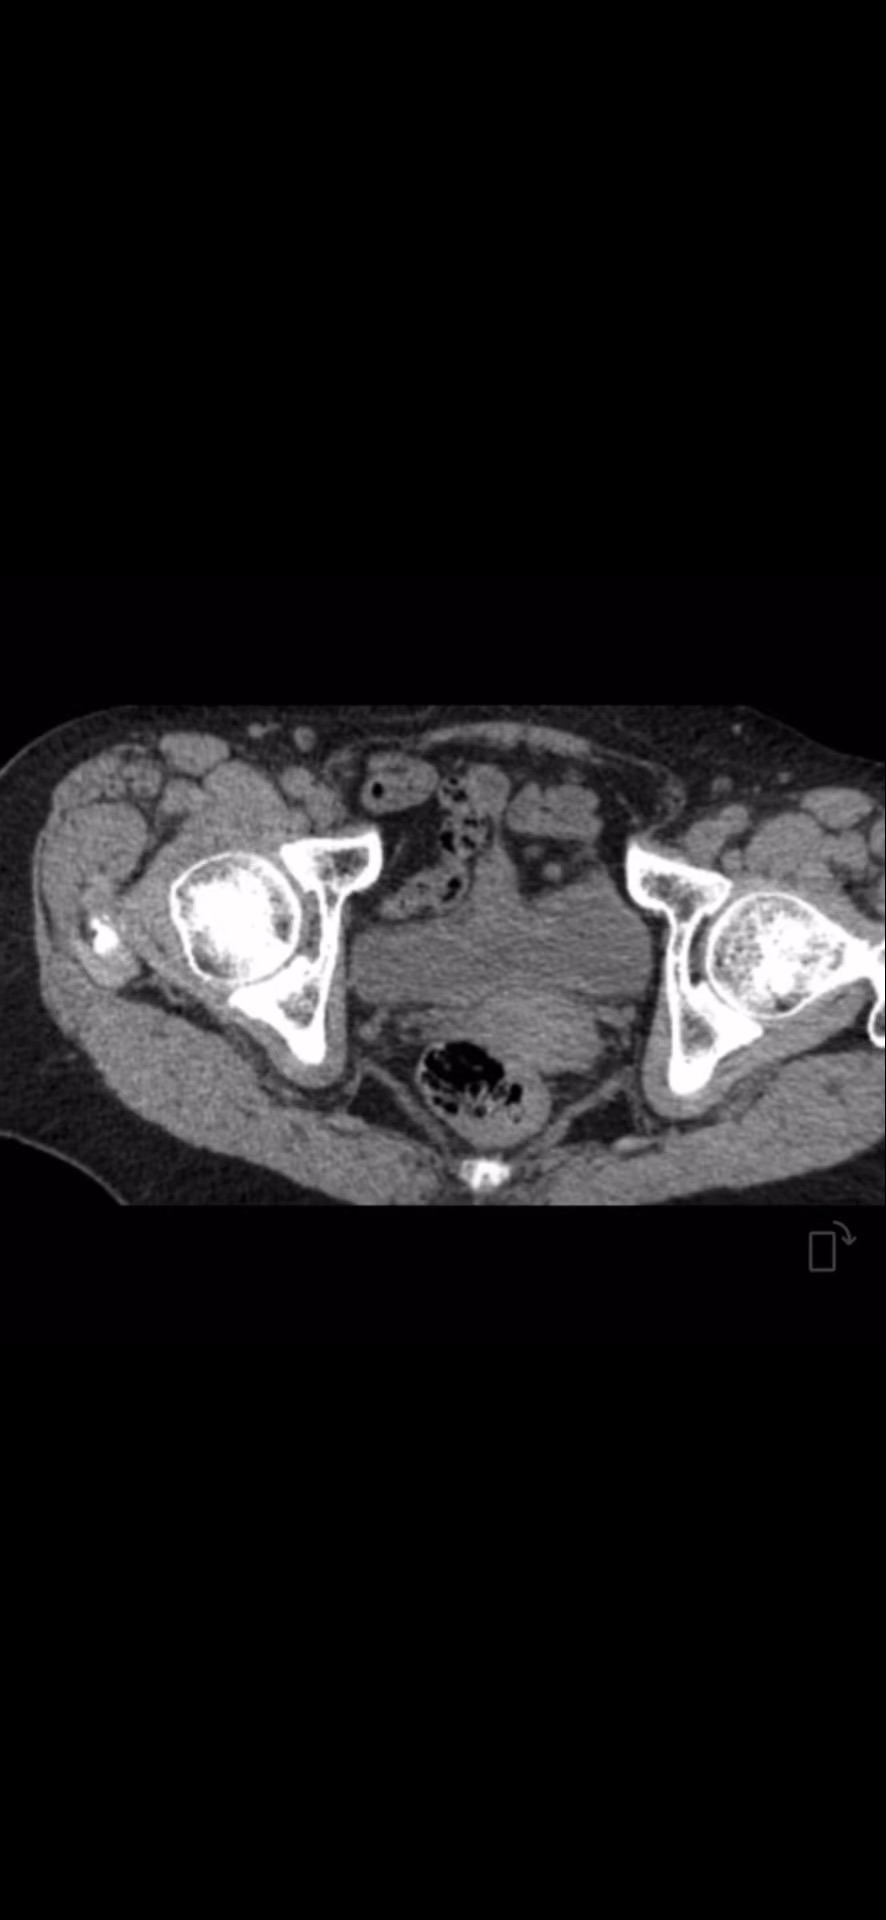

CT: